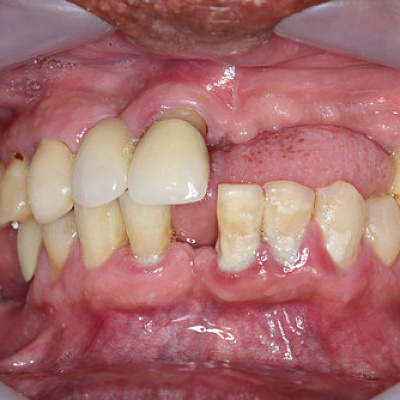

Хронические формы заболевания протекают более агрессивно. Это касается и обострений патологического процесса. Особенность патологии в том, что она часто поражает ткани и вызывает из изменения. Нередко образуются гранулемы и крупные кисты. Лечение хронического периодонтита обычно оперативное, хирургическое. Когда зуб еще можно сохранить, проводится резекция верхушки корня или полное удаление корня. Однако это не гарантия клинического результата. Часто зуб сохранить невозможно. Тогда проводится удаление. После коррекции состояния лунки, устранения воспалительного процесса решают вопрос имплантации или иного протезирования.